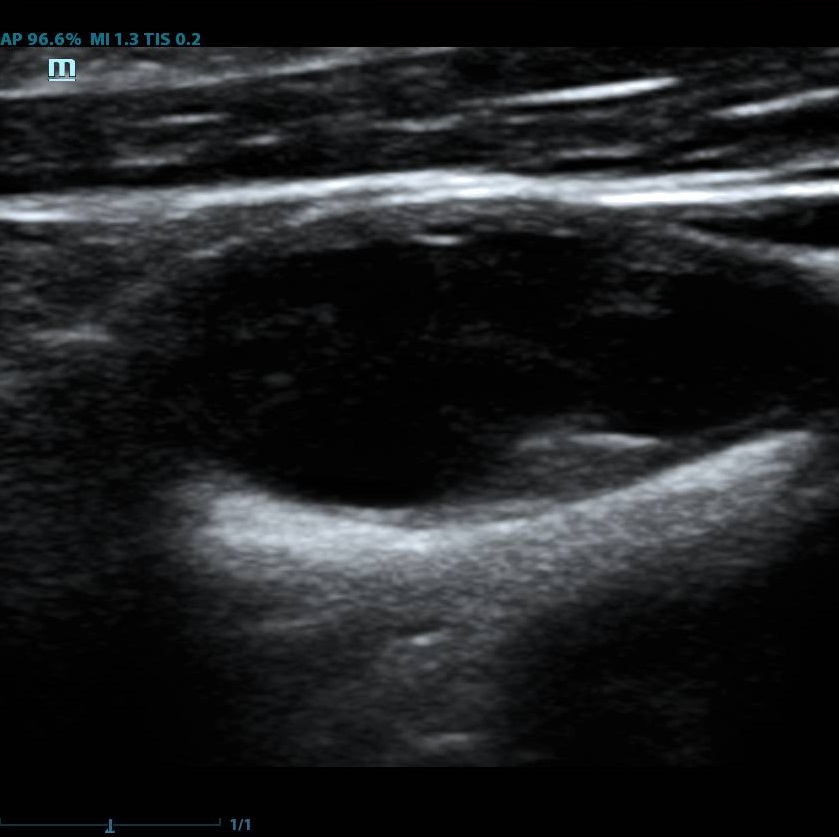

Помимо базовых целей по выявлению атеросклероза, бляшек, оценки кровотока и значимости стеноза, врачу ультразвуковой диагностики ставится и множество других задач при исследовании сонных артерий. Одна из них – оценка стабильности бляшки.

Современное решение – компьютерный анализ структуры бляшки. Ультразвуковая система экспертного класса Mindray DC-8 способна провести программный анализ полученного изображения бляшки и дать количественную оценку её структуры. Для этого используется показатель GSM – Grey Scale Median. Прибор рассчитывает медиану по показателям серой шкалы в выделенной зоне и выдает данные в виде графика распределения эхогенности и числовых данных для количественной оценки. Таким образом, исследование становится более объективным и воспроизводимым, снижается зависимость от оператора (человеческого фактора).